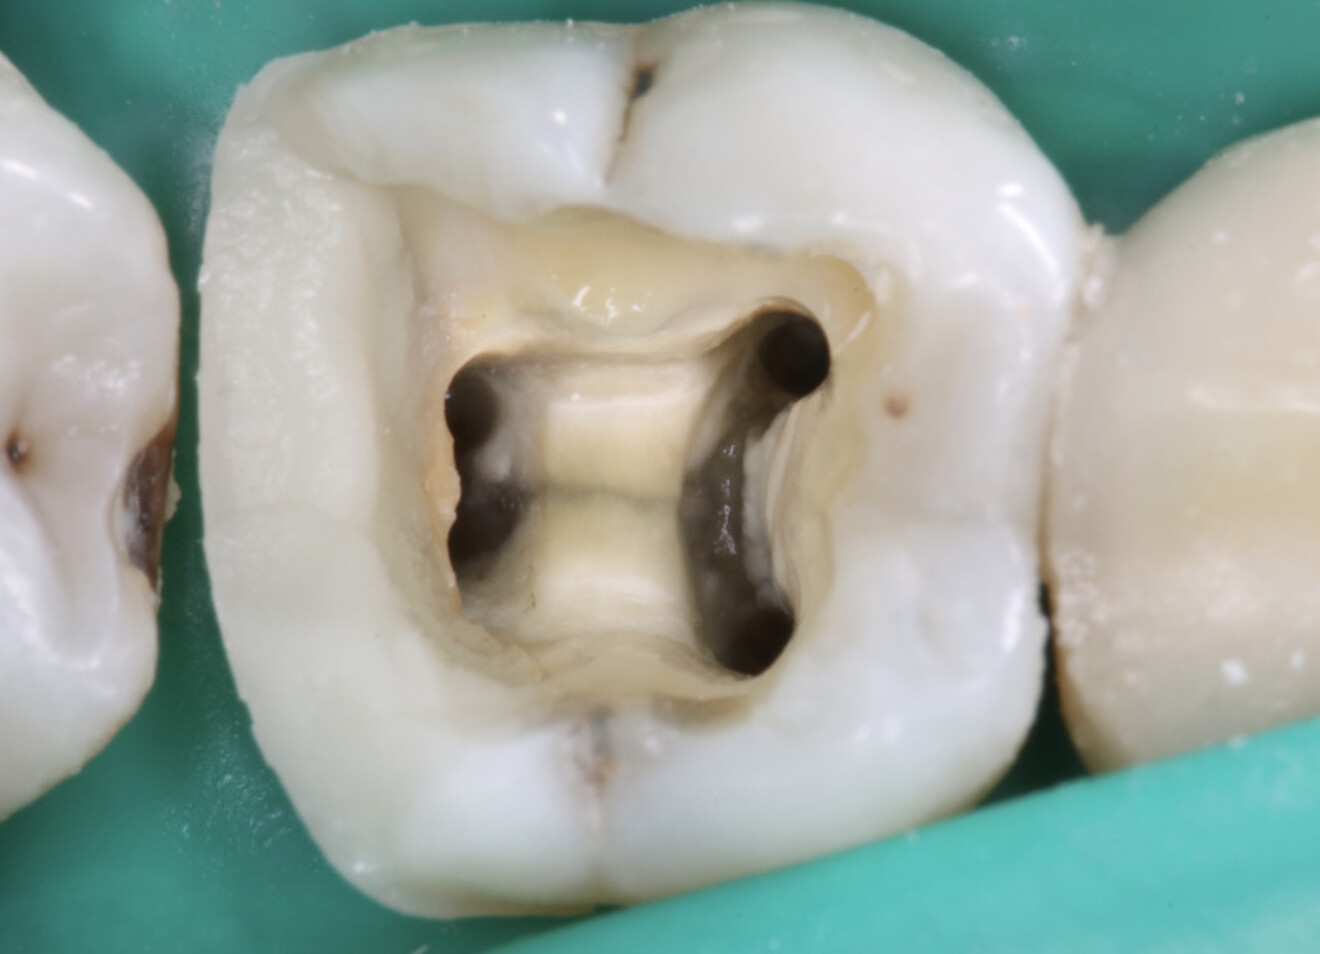

D’un point de vue pratique, la première étape consiste à réduire les dimensions du tenon s’il occupe une grande partie de la structure coronaire, de préférence en lui donnant une forme cylindrique similaire à celle d’un tenon préfabriqué. De même, une reconstitution corono-radiculaire coulée ancrée dans plusieurs canaux doit d’abord être sectionnée jusqu’au niveau du plancher de la cavité pulpaire, afin de la traiter comme un ensemble de tenons unitaires, ce qui diminue le degré de rétention global du système. La réduction du tenon doit être effectuée avec des fraises en carbure spécialement conçues pour découper le métal, sous une irrigation abondante. Les évaluations cliniques et radiographies préliminaires sont essentielles pour planifier l’angle de coupe. La procédure doit être fréquemment vérifiée et, si nécessaire, il convient d’effectuer des contrôles radiographiques avant qu’une quantité excessive de dentine ne soit sacrifiée (Figs. 1–3).